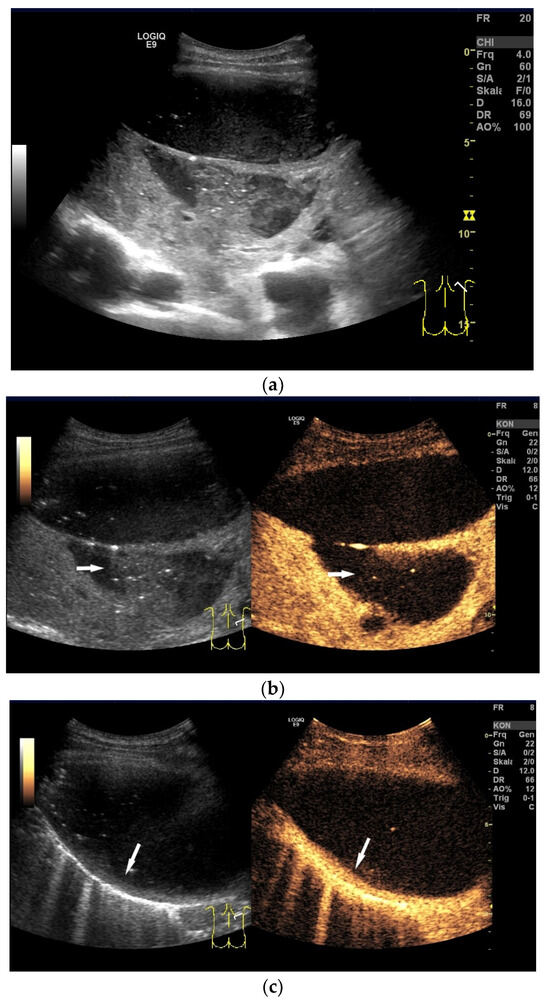

| Tuberculous pleuritis | Pleura effusion with fibrin strands, pleural calcification, and thickening. Hypoechoic granulomatous inflammation and granulomas with hyper-enhancement on CEUS in thickened pleura. Hypoechoic caseous abscesses in thickened pleura, hypo- or nonenhanced, heterogeneously enhanced lesions, with contrast-enhanced septations and contrast-enhanced rim. |

- Sun, W.; Zhou, Y.; Li, W.; Wang, Y.; Xiong, K.; Zhang, Z.; Fan, L. Diagnostic yield of Xpert MTB/RIF on contrast-enhanced ultrasound-guided pleural biopsy specimens for pleural tuberculosis. Int. J. Infect. Dis. 2021, 108, 89–95. [Google Scholar] [CrossRef]